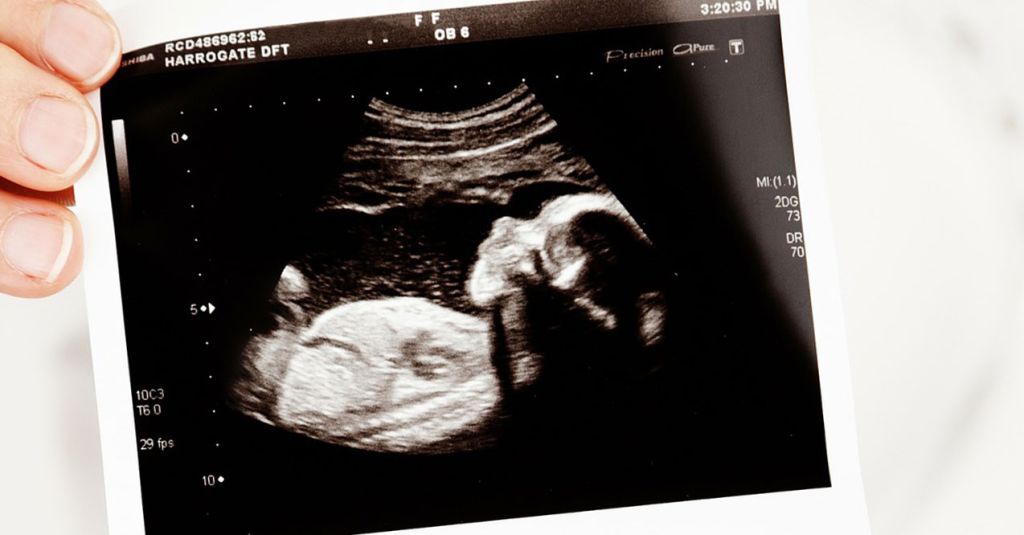

It was a BIG day yesterday! Producer Nick was very surprised to find an ultrasound on his counter!